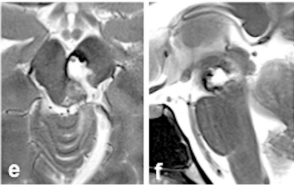

在手术暴露时,被盖外侧表面正常;箭头表示滑车神经的走行(g)。脑海绵状血管瘤完全切除后的术中照片显示2毫米尺度的空切除术腔(h)。术后轴向(e)和矢状(f)MRI证实病灶完全切除。

术后MRI